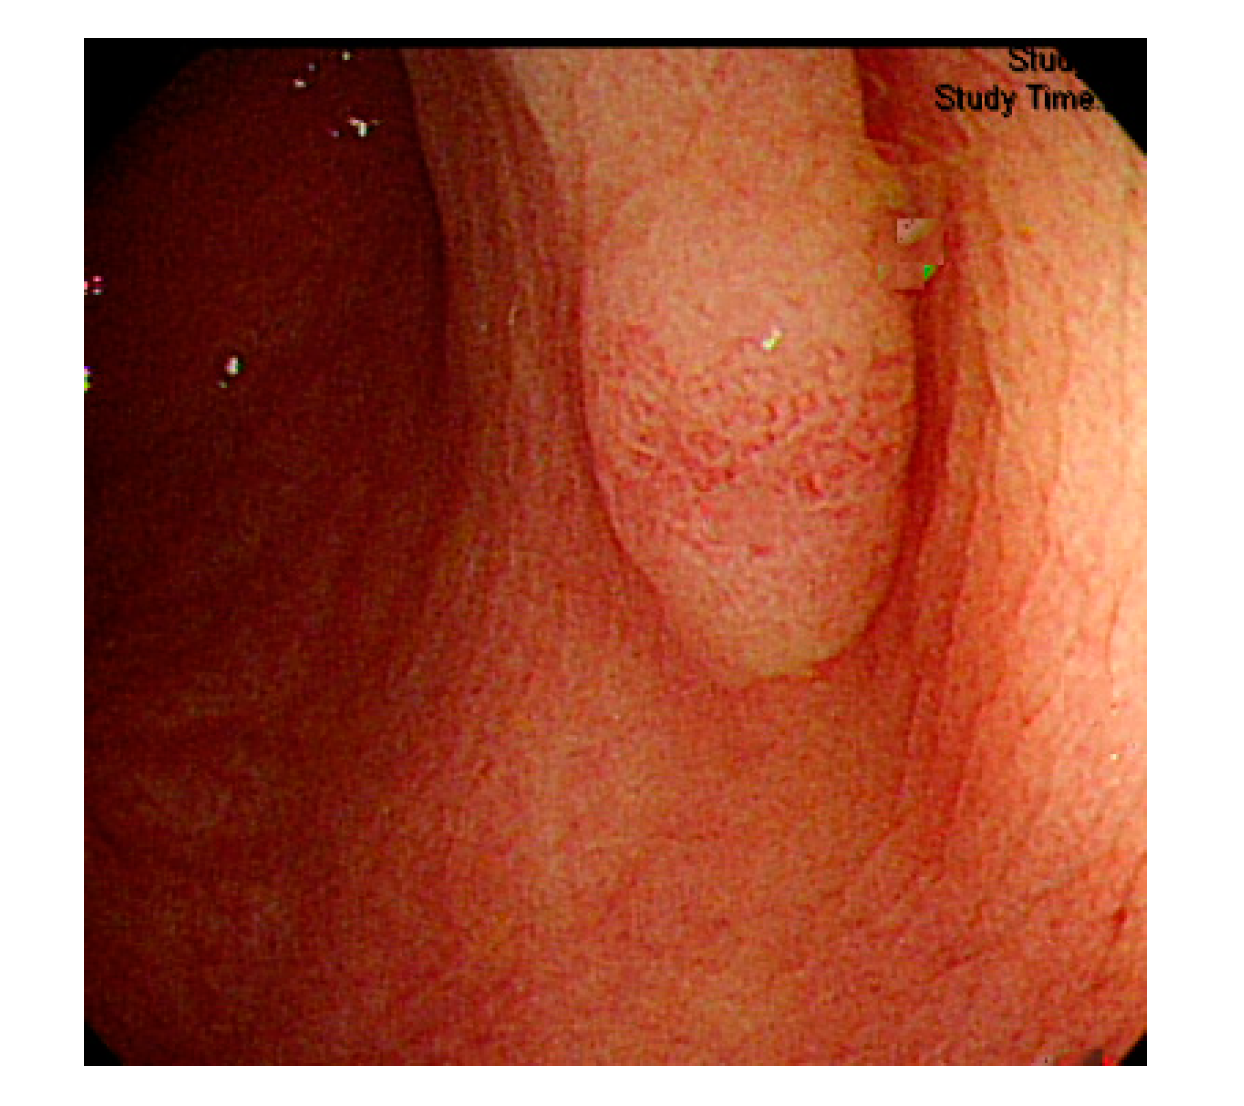

Currently, many medical images are processed into grayscale images, such as ultrasound, computed tomography (CT), and magnetic resonance (MR) images. Tan et al. [44] applied a gray-level cooccurrence matrix and CNN to CT images for polyp diagnosis. Zhang et al. [45] compress the three-channel color images of chest CT to grayscale images. A five-layer deep CNN with stochastic pooling is used to diagnose chest-based COVID-19. Xie et al. [46] mentioned that in deep learning, colors are not the key features influencing accurate image classification. They also discovered that in X-ray image classification, the speed and accuracy of processing grayscale images were considerably higher than those of processing RGB images. The grayscale method used was ITU-R Recommendation BT.601 [47]. Moreover, misjudgments were easily made in the presence of excessive intestinal wall textures, when polyps were too small (Figure 2), and when polyp textures were similar (Figure 3) to intestinal wall textures.

Figure 2.

Excessive intestinal wall textures with small polyps.